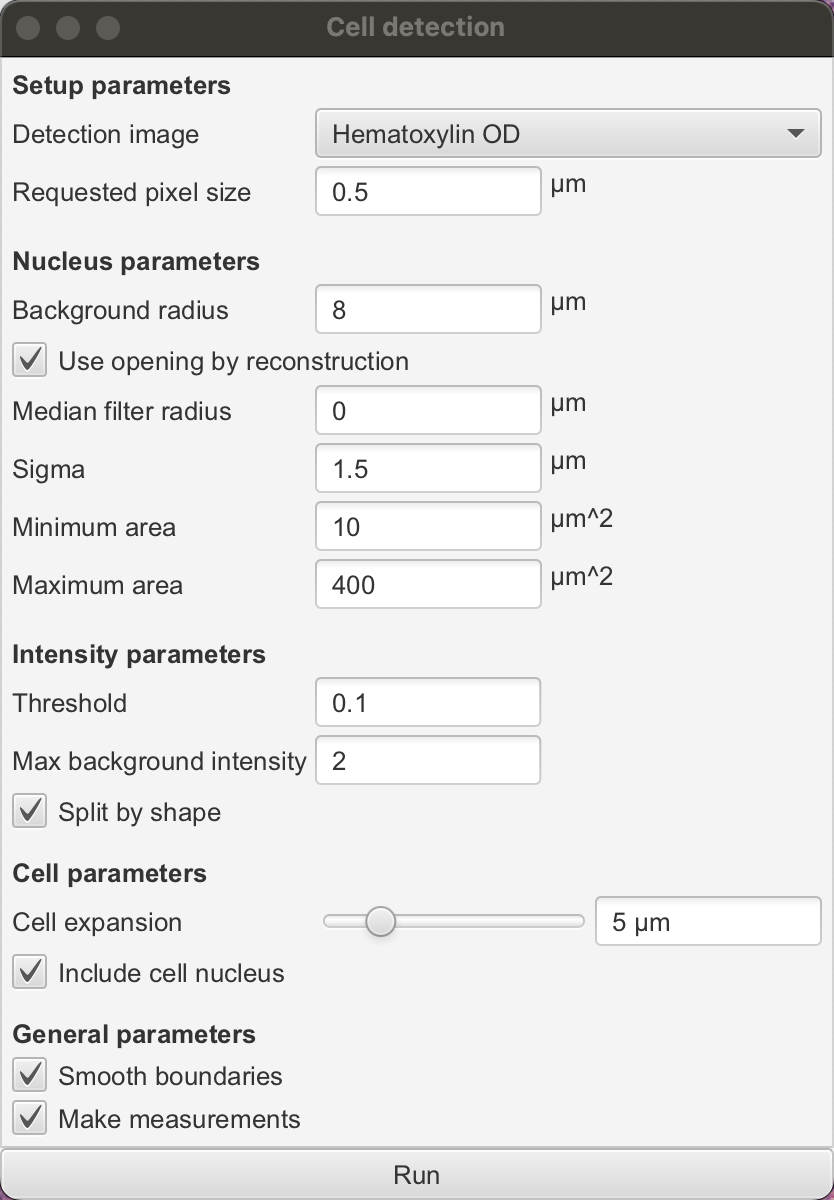

运行“Analyze ‣ Cell detection ‣ Cell detection”命令。

这应该会显示一个令人望而生畏的参数列表,以适应不同图像的检测。

如果您愿意,可以探索这些参数,并在鼠标悬停在每个参数上以获取描述——但现在,您也可以忽略它们并使用默认值(这些默认值通常在各种图像上表现得相当合理)。

点击对话框底部的“运行”按钮。几秒钟后,您所选区域中的细胞应该会出现。这些细胞是您的第一个检测对象。